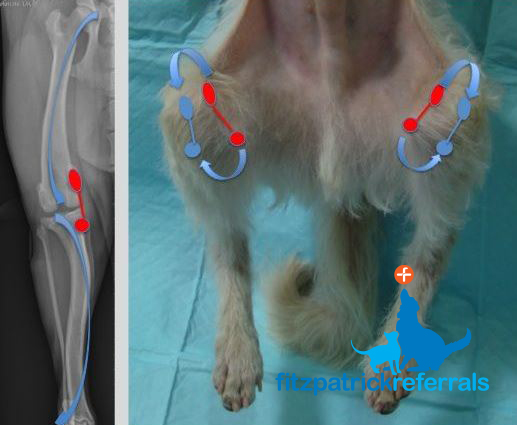

Knee dislocation Wikipedia sale, Knee Dislocation Trauma Orthobullets sale, Knee Dislocation Practice Essentials Prognosis sale, Knee dislocation Wikipedia sale, Luxating patella in dogs PDSA sale, Anterior knee dislocation Radiology at St. Vincent s University sale, Knee Dislocation Trauma Orthobullets sale, Luxating Patella in Dogs Knee Dislocation Symptoms Causes sale, Knee joint dislocations illustrations Radiology Case sale, Dislocated Knee Hartford Hospital Hartford CT sale, Knee Dislocation Practice Essentials Prognosis sale, Knee Dislocation Orthopaedic Trauma Association OTA sale, Knee Dislocation Multi ligament Knee Injuries Lamberti sale, Patellar dislocation Physiopedia sale, Kneecap Dislocation sale, All About Knee Dislocations USF Emergency Medicine sale, Patellar Subluxation Subluxed Partially Dislocated Kneecap Facts sale, Knee dislocation Radiology Reference Article Radiopaedia sale, Posterior knee dislocation Radiology at St. Vincent s University sale, Two years neglected knee dislocation An unusual case report sale, Knee Dislocation Orthopaedic Trauma Association OTA sale, Dislocated Knee Knee Surgeon Minnesota sale, Knee Dislocation Orthobridge Orthopaedic Institute sale, True Knee Patellar Dislocations Core EM sale, Kneecap Dislocation Patellar Subluxation Treatment Symptom Causes sale, Patellar dislocation LITFL Trauma Library sale, Knee dislocation Radiology Case Radiopaedia sale, Patella luxation in dogs Joii Pet Care sale, Medial Patella Luxation Queensland Veterinary Specialists sale, Patella Luxation Warren House Veterinary Centre sale, Patellar luxation Marshalswick Veterinary Surgery sale, Patella Luxation Smart Approach Veterinary Services sale, Patellar luxation Fitzpatrick Referrals sale, Patellar Dislocations Everything You Need To Know Dr. Nabil Ebraheim sale, Medial Luxating Patella Grades of Dislocations Surgery and sale.